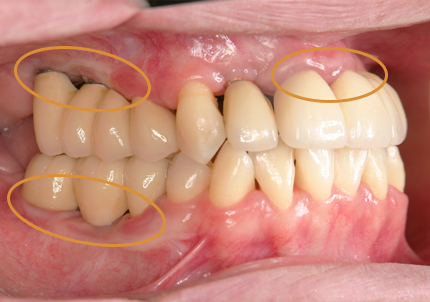

1.初診時口腔内(2007年6月30日)

8.初診より現在に至る

強い歯ぎしり、くいしばりで奥歯の歯牙破折、深い虫歯で保存不可能となり全顎治療となる。

↑ 2007年6月30日(初診)

↑ 2025年9月9日

治療後は経過良好